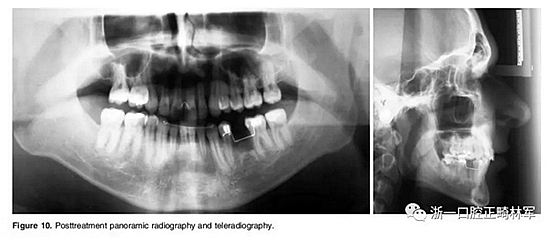

全景片顯示牙根平行度良好、無(wú)吸收。此外,在左下第二前磨牙的區(qū)域獲得了用于植入種植體修復(fù)的良好空間。頭顱側(cè)位片和疊加顯示,上下切牙傾斜度以及前后和垂直向位置的變化也很大(Figure 10、11; Table 1)。